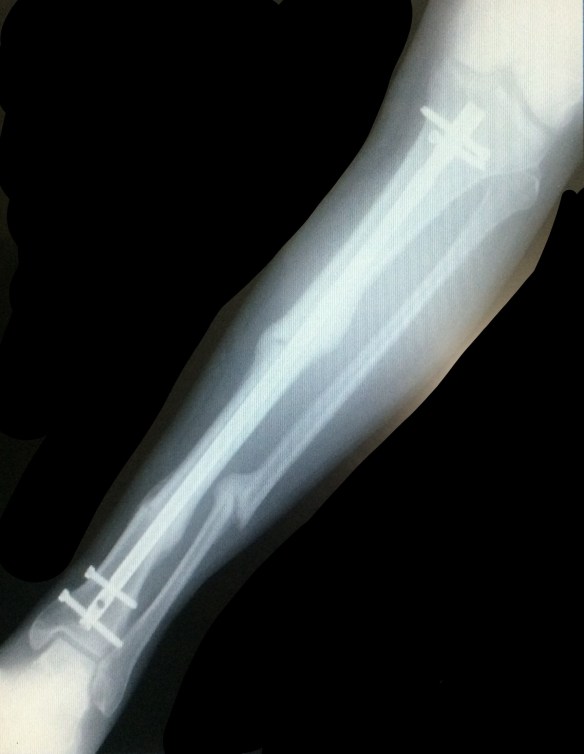

X-ray from May 21, 2015, 7 months after Jeffrey’s leg was shattered by an SUV driver’s crime. Three breaks, 1 titanium rod, 4 screws, some clouds of new bone. Two days after this x-ray was taken, we left on the Ride to New England.

On the 2013 Ride, we averaged 70 miles per day. In 2014, we averaged 78 miles. In 2015, 7 months post-crash, we could average only 56 miles. How the mighty have fallen!